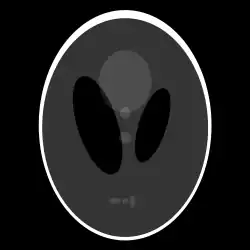

If a function represents an unknown density, then the Radon transform represents the projection data obtained as the output of a tomographic scan. The inverse of the Radon transform can be used to reconstruct the original density from the projection data, and thus it forms the mathematical underpinning for tomographic reconstruction, also known as iterative reconstruction.

The process of reconstruction produces the image (or function in the previous section) from its projection data. Reconstruction is an inverse problem.

Explicit and computationally efficient inversion formulas for the Radon transform and its dual are available. The Radon transform in dimensions can be inverted by the formula:[11] where , and the power of the Laplacian is defined as a pseudo-differential operator if necessary by the Fourier transform: For computational purposes, the power of the Laplacian is commuted with the dual transform to give:[12] where is the Hilbert transform with respect to the s variable. In two dimensions, the operator appears in image processing as a ramp filter.[13] One can prove directly from the Fourier slice theorem and change of variables for integration that for a compactly supported continuous function of two variables: Thus in an image processing context the original image can be recovered from the 'sinogram' data by applying a ramp filter (in the variable) and then back-projecting. As the filtering step can be performed efficiently (for example using digital signal processing techniques) and the back projection step is simply an accumulation of values in the pixels of the image, this results in a highly efficient, and hence widely used, algorithm.